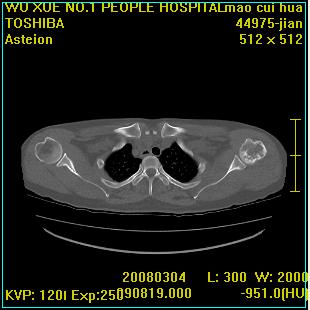

标题: CT12025:男,50岁,左肩活动受限半年。 [打印本页]

标题: CT12025:男,50岁,左肩活动受限半年。

能有x线平片就好了。肱骨头骨结构有破坏。

肩关节骨质破坏呈小囊状,其周软组织轻度肿胀,余未见异常。

考虑:肩袖损伤。建议mri。

左侧肱骨头密度不均匀,高低混杂,周围软组织略肿胀,考虑结核性病变。

考虑左侧肱骨慢性骨髓炎。

左侧肱骨头密度不均匀,高低混杂,髓腔密度稍高,周围软组织略肿胀,肌间隙模糊,考虑慢性骨髓炎可能。密切结合临床!